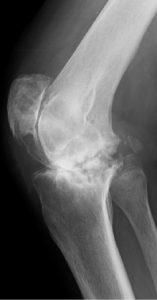

术前(左)和术后(右)关节X光图片病人三年来第一次外出手术

连续142名RA病历(201膝盖)从1997年8月22日到2011年3月16日拥有初级TKA所有程序均由单科外科医生在单一机构进行普通麻醉,所有病人都由同一名医生治病。79名病人口服类固醇,82名病人外科时服甲状腺素22名病人同时使用肿瘤消毒因子对立法处理TKATKA后,59名病人接受了生物治疗初级TKA后,106名病人单从膝部外科手术,其余36名病人额外接受低端联合外科手术,如全流节肢科全科全科全科全科节肢科全科全科全科全科全科全科全科全科全科全科全科全科全科全科全科全科全科全科全科全科全科全科全科全科全科全科全科全科全科全科全科全科全科全科全科全科全科全科全科全科全科全科全科全科全科全科全科全科全科全科全科全科全科全科全科全科全科全科全科全科全科全科全科全科全科全科全科全科全科全科全科全科全科全科全科全科全科全科全科全科全科全科全科全科全科全科全科全科全科全科全科提交者附属机构IRB(机构评审委)批准此项研究

Genesis2(Smith和Nephew,Memphis,TN,USA)在所有例子中都使用假肢类型,1997年8月首次提交115名病人(164个植入式)受难保留TKAs,25名病人(35个植入式)后稳定TKAs,2名病人修改TKAs(2个植入式)。术后第1天,所有案例都应用扩展膝盖支架,并开始ROM运动演练、连续被动运动和增强肌肉活动重生手术第二天允许使用,3周后开始爬楼梯开通T-Cane并忍受上行楼梯后,所有病人都出院

所有病人都评估成日本矫形协会评分(JOA评分)、活动ROM、X光检测结果、RA活动、户外振荡持续时间和移植累积生存率以百分位标度 JOA分数测量疼痛范围 手动肌肉测试 编译能力 爬楼梯能力疼痛标记40分 ROM标记12分 四叉肌肉强度标记20分 步行能力值20分 爬楼梯值8分JOA85或85以上评分被视为优异、70-84良好、60-69公平并低于60穷